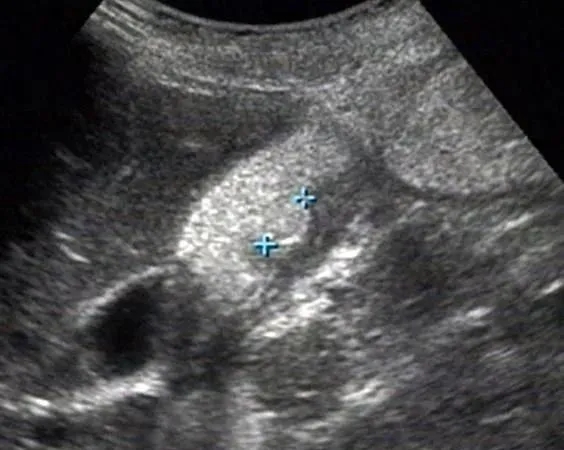

十二指肠球前壁溃疡